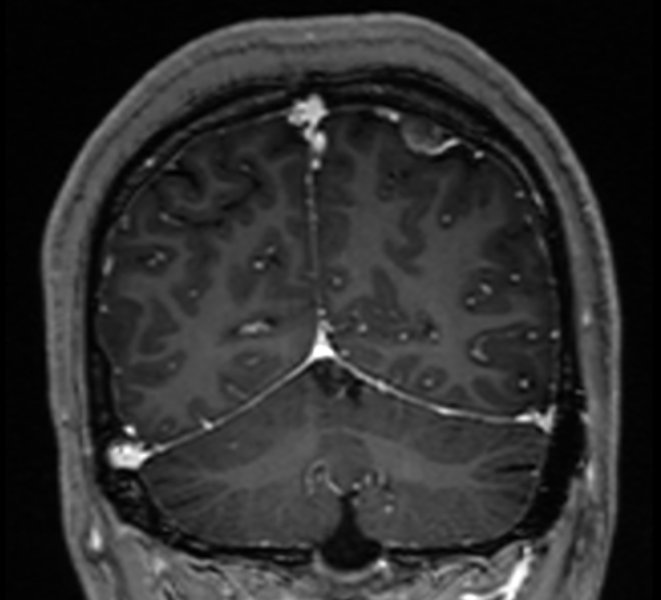

入院后,医院为她进行了详尽的颅脑MRI增强及头颅CT薄扫检查,结果显示其病变位于左侧顶上小叶,病变对脑组织压迫明显(病变周围脑组织CBF灌注明显降低、较对侧脑回体积明显减小),且与左侧大脑上静脉紧密相关,动态视频脑电图分析进一步提示病灶周围脑组织存在异常放电。

术前MRI冠状位图像

术前MRI提示左侧中央后回较对侧稍小。